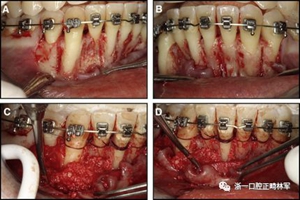

粘合保持器被移除,并放置固定裝置(圖15),僅限于患者要求的下頜弓。在第一階段牙周過程中,將結締組織移植物置于下頜右側中切牙的面側。2個月后進行第二階段牙周過程(圖16)。包括有意識的垂直骨質評分以啟動區域加速現象,以及顯著的面側和舌側植骨以糾正骨開窗。隨著時間的推移,全維度弓絲及其表達的牙齒間扭矩差異顯著改善(圖17)。明智的鄰間減少之后,間隙關閉擴大接觸面,消除不美觀的黑三角。在脫粘之前也校正了牙齒排列和牙弓形態(圖18)。之前和之后的三維圖像(圖19)突出顯示在下頜右側尖牙面側表面上骨的增加以及前牙牙根位置的改善。由于下頜切牙的伸長被認為是不嚴謹的,因此輕度前牙開合沒有被矯正。

圖16.第二階段牙周手術階段,軟組織移植后2個月:A和B,這包括應用骨形態發生蛋白,故意骨質損傷引起局部加速現象,以及C和D,應用植骨漿液糾正牙槽骨的開窗(Colin Richman博士提供)。